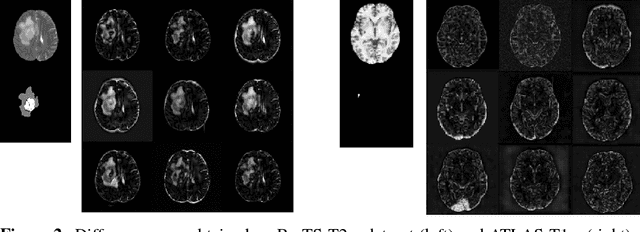

Abstract:Recent advances in deep learning led to novel generative modeling techniques that achieve unprecedented quality in generated samples and performance in learning complex distributions in imaging data. These new models in medical image computing have important applications that form clinically relevant and very challenging unsupervised learning problems. In this paper, we explore the feasibility of using state-of-the-art auto-encoder-based deep generative models, such as variational and adversarial auto-encoders, for one such task: abnormality detection in medical imaging. We utilize typical, publicly available datasets with brain scans from healthy subjects and patients with stroke lesions and brain tumors. We use the data from healthy subjects to train different auto-encoder based models to learn the distribution of healthy images and detect pathologies as outliers. Models that can better learn the data distribution should be able to detect outliers more accurately. We evaluate the detection performance of deep generative models and compare them with non-deep learning based approaches to provide a benchmark of the current state of research. We conclude that abnormality detection is a challenging task for deep generative models and large room exists for improvement. In order to facilitate further research, we aim to provide carefully pre-processed imaging data available to the research community.